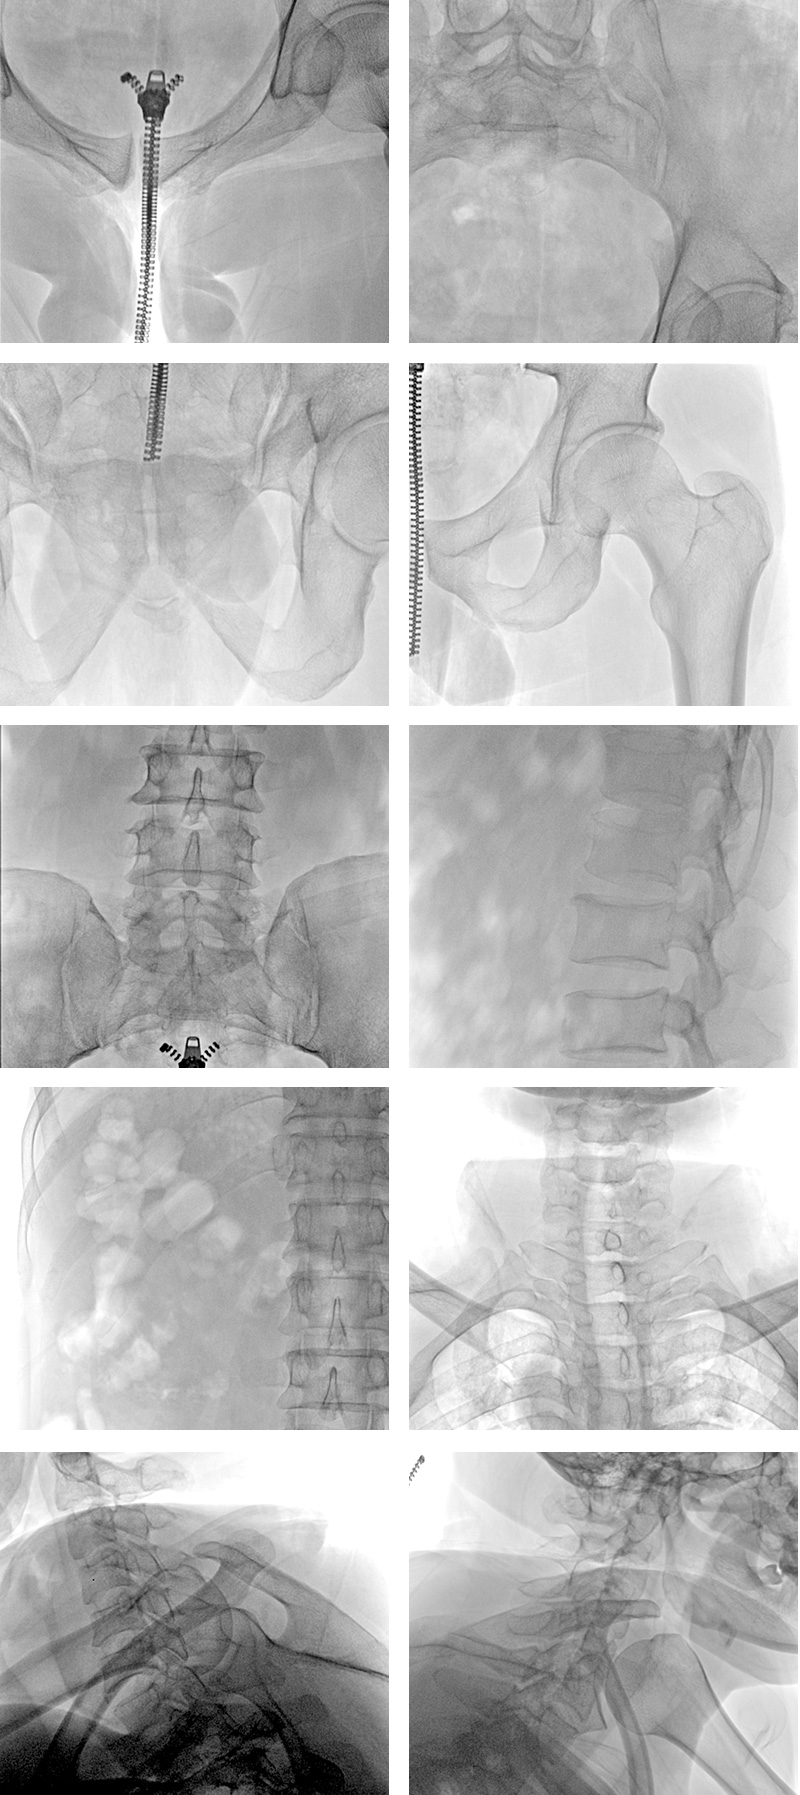

臨床圖片展示

精簡于形,技善于視?!疤炷俊逼桨逍臂堅守現(xiàn)代骨科臨床高標(biāo)準(zhǔn)、高水準(zhǔn)的診斷要求,保證高清無損的數(shù)字影像圖像和強大便捷的整機操控性能。